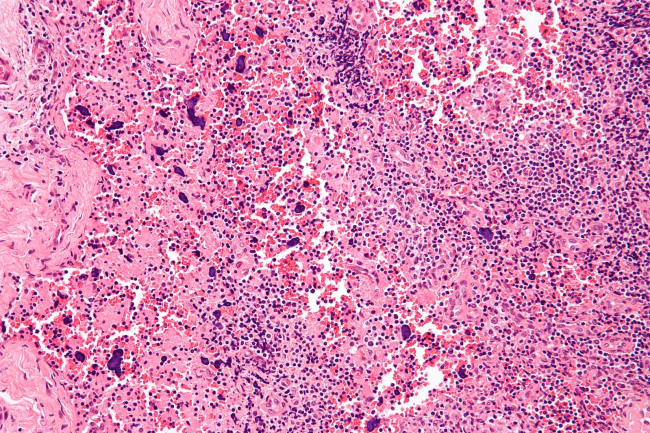

systemic lupus erythematosus

Dr. Shivani Garg leads the state's only lupus clinic